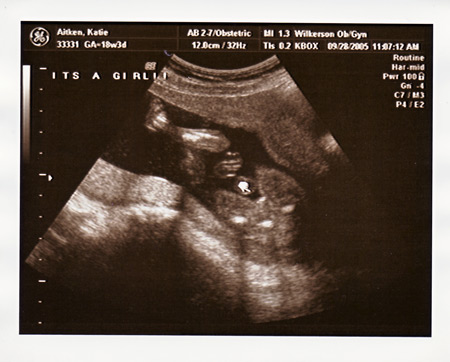

I had my ultrasound today, and found out everything is perfect and in place. We are so excited that Maeve will have a little sister to play with!!!